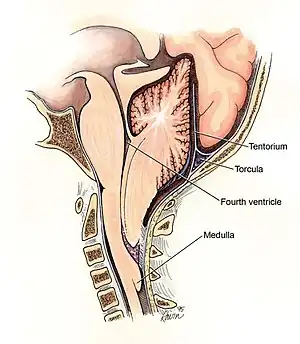

Este tipo, también denominado malformación de Chiari clásica o malformación de Arnold-Chiari propiamente dicha, involucra la protrusión de estructuras cerebelosas y también del tallo cerebral a través del foramen. A menudo el vermis está, además, incompleto o ausente, y todo el cuadro suele acompañarse de hidrocefalia y mielomeningocele a nivel lumbar. Esta complicación puede derivar en parálisis parcial o total por debajo del mielomeningocele.[8]

La forma más grave de la anormalidad. El cerebelo y el tallo cerebral, herniados, se introducen en el canal medular cervical, a menudo acompañados del cuarto ventrículo cerebral y comprimen la médula espinal. En algunos casos raros, el tejido cerebeloso herniado asoma por una abertura anormal del hueso occipital, formando una bolsa llamada encefalocele occipital, que puede contener incluso tejido cerebral. Este tipo de Chiari produce serios síntomas neurológicos.